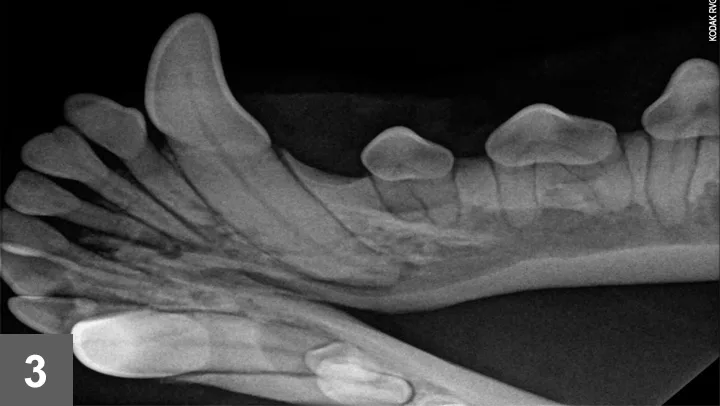

Full-mouth dental radiographs were taken (Figures 2 and 3).

Figure 3: Dental radiograph of the left rostral mandible

Missing TeethMissing teeth are more often found in brachycephalic breeds and most commonly involve the first premolar teeth.5,6 Radiographs should be taken for every missing tooth. Finding an unerupted tooth with or without an associated cyst is an important finding that could otherwise go unnoticed, thereby allowing significant structural changes to the jaw bone before outward clinical signs are noted.